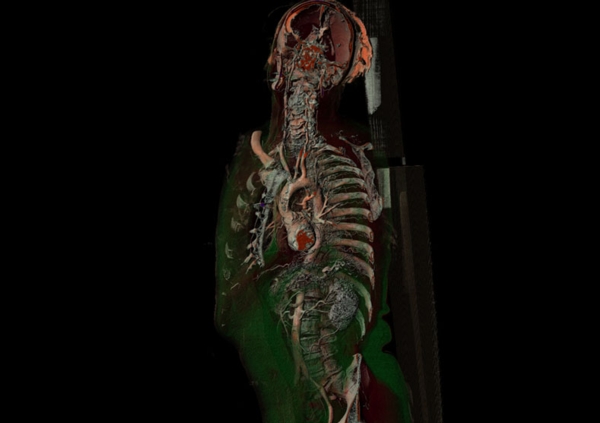

在随后的幻灯片中,您将看到来自瑞典医学图像科学与可视化中心(the Center for Medical ImageScience and Visualization ,CMIV)的Anders Persson和他的同事们运用CT,MRI和超声得到的令人惊叹的尸检图片。这些图片描绘了人体骨骼,消化道,循环系统和大脑以及野猪的前端结构。

1, 人体,侧身;骨骼和心血管系统清晰可见。